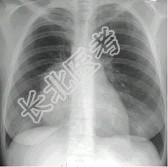

- 单项选择题女,18岁, 自感胸闷,X光检查见纵隔占位, CT检查如图,最可能的诊断为 ( )